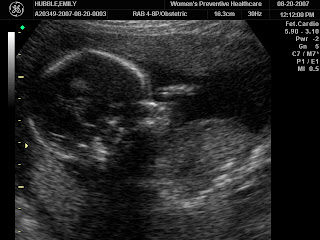

The Ultrasound!

These are side views. The baby has its arm up touching its nose in the top picture :) It was moving around a lot! We decided to not find out the sex of the baby, so it will be a big surprise when we deliver in January. I'm 20 weeks...so halfway there!!